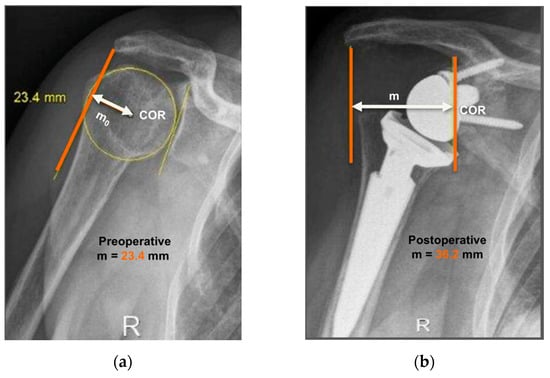

2.3. Radiographic Evaluation

- Lädermann, A.; Williams, M.D.; Melis, B.; Hoffmeyer, P.; Walch, G. Objective evaluation of lengthening in reverse shoulder arthroplasty. J. Shoulder Elbow Surg. 2009, 18, 588–595. [Google Scholar] [CrossRef]